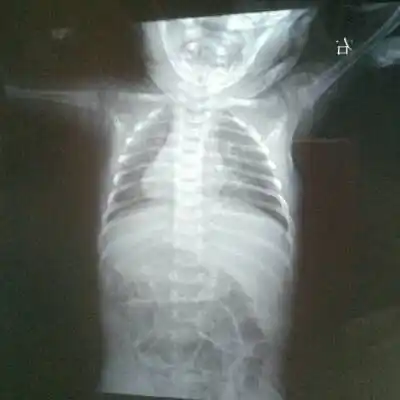

新生儿30天得肺炎,现在在妇幼icu,这是胸片,很严重吗

图片尺寸400x400